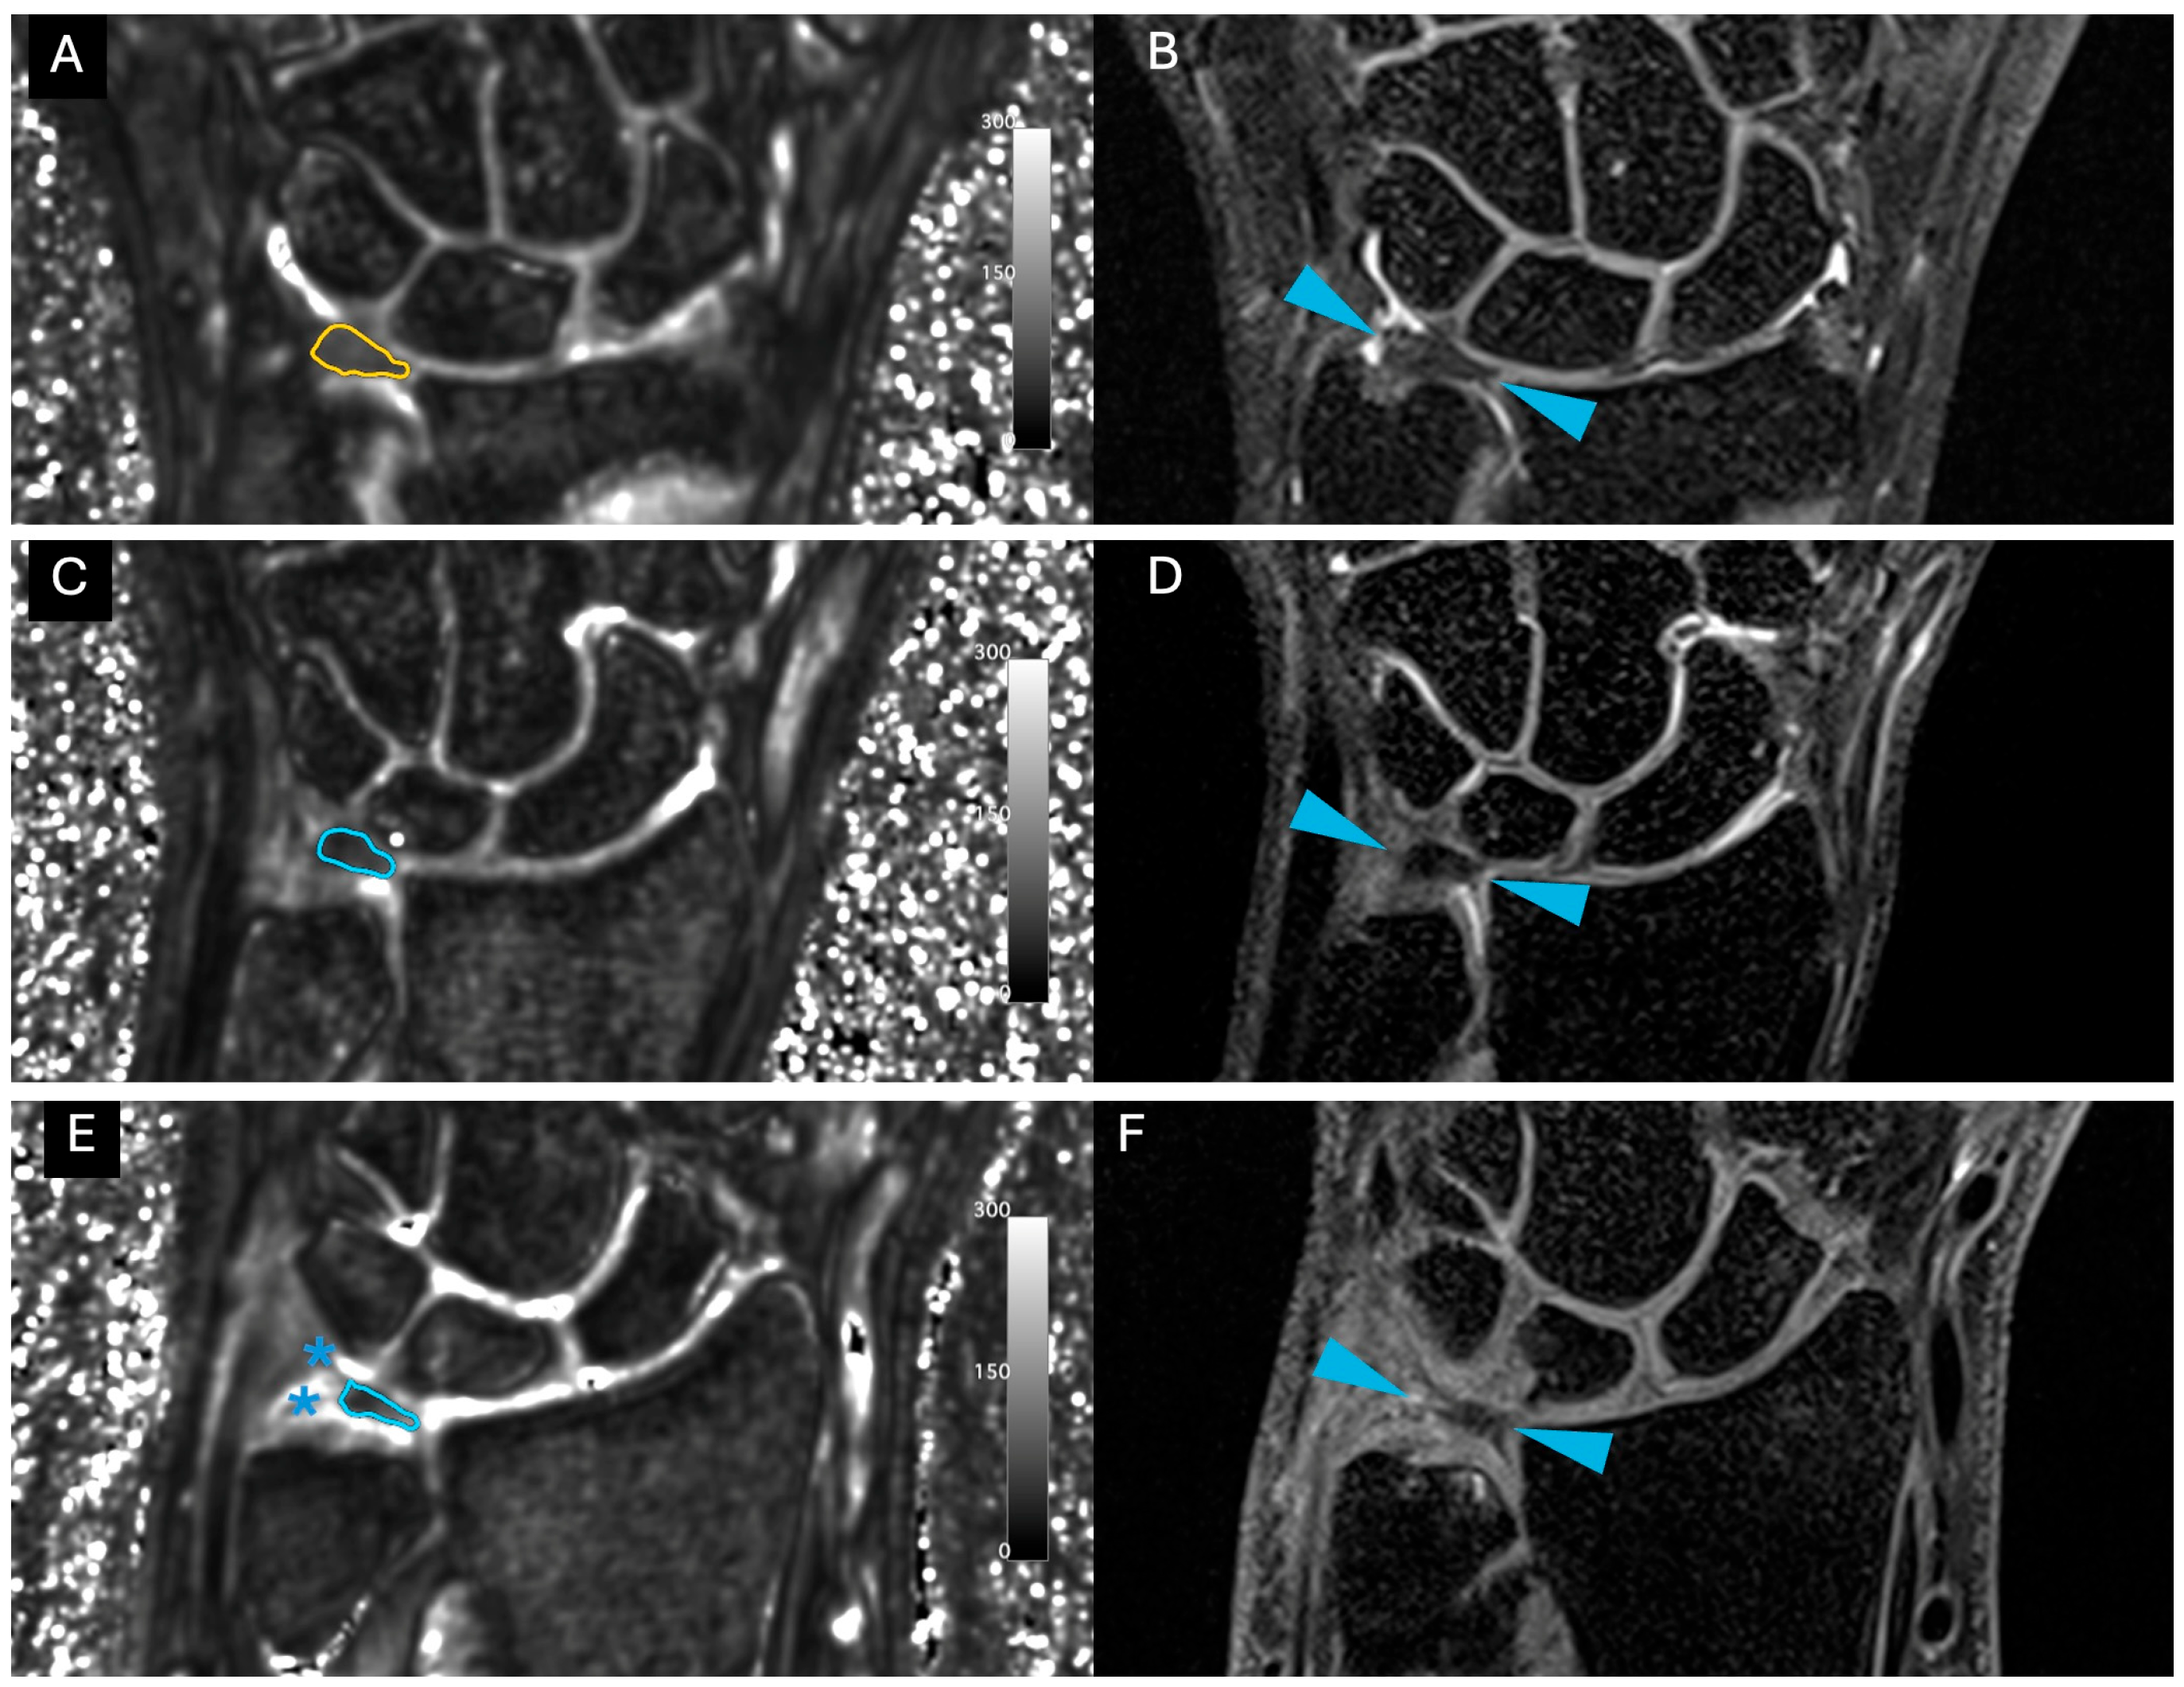

Images were free of artefact, allowing optimal visualization of the TFCC in all cases. No cases of central TFC perforation or additional TFCC injuries were detected. An example of the sequences acquired for one volunteer is shown in Figure 1. Figure 2 presents the multiple echoes of the 3D UTE-T2* mapping sequence along with the resulting UTE-T2* map. TFC segmentation on a single slice of the UTE-T2* map is illustrated in Figure 3 for three volunteers with different ages.

Figure 3. Visualization of a representative slice of the TFC disc for three different volunteers. (A,C,E): corresponding slice on the 3D UTE-T2* map with windowing parameters set between 0 and 300 a.u., corresponding to 0 and 30 ms. The manual contouring of the disc is shown in color. Stars indicate tendons that were excluded from the disc segmentation. (B,D,F): corresponding 3D PD SPACE with fat suppression in the coronal orientation. Fat suppression helps distinguish fluids from fat, as the latter is also hyperintense. Blue arrows indicate TFC. From top to bottom, the volunteers were 22, 33 and 48 years old, respectively.